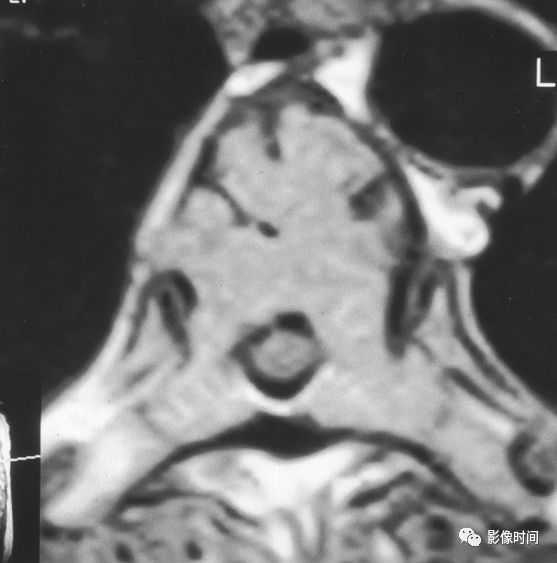

18哑铃征

哑铃征(Dumbbell sign),又称脊柱肿瘤哑铃样表现(Dumbbell appearance of spinal tumors)

所谓哑铃征指的是肿瘤既有椎管内部分也有椎旁部分,其通过椎间孔的部分缩窄(红箭),形似哑铃型,故而得名。此征象最常见于神经鞘瘤,还可以见于神经纤维瘤、神经节细胞瘤、神经母细胞瘤或者脊膜瘤等。

典型病例

病例 1,神经鞘瘤,MRI 横轴位 T1WI 及 T2WI 像示神经鞘瘤跨椎管内外,呈现哑铃征。

病例 2,神经鞘瘤。MRI 横轴位 T2WI 脂肪抑制及 T1WI 增强扫描脂肪抑制像示神经鞘瘤跨椎管内外,呈现哑铃征。

引用自:1.https://radiopaedia.org/articles/dumbbell-appearance-of-spinal-tumours2. https://radiopaedia.org/articles/ spinal-schwannoma

3. Tomii M,Itoh Y,Numazawa S. Surgical consideration of cervical dumbbell tumors. Acta Neurochir (Wien) 2013; 155: 1907-1910.